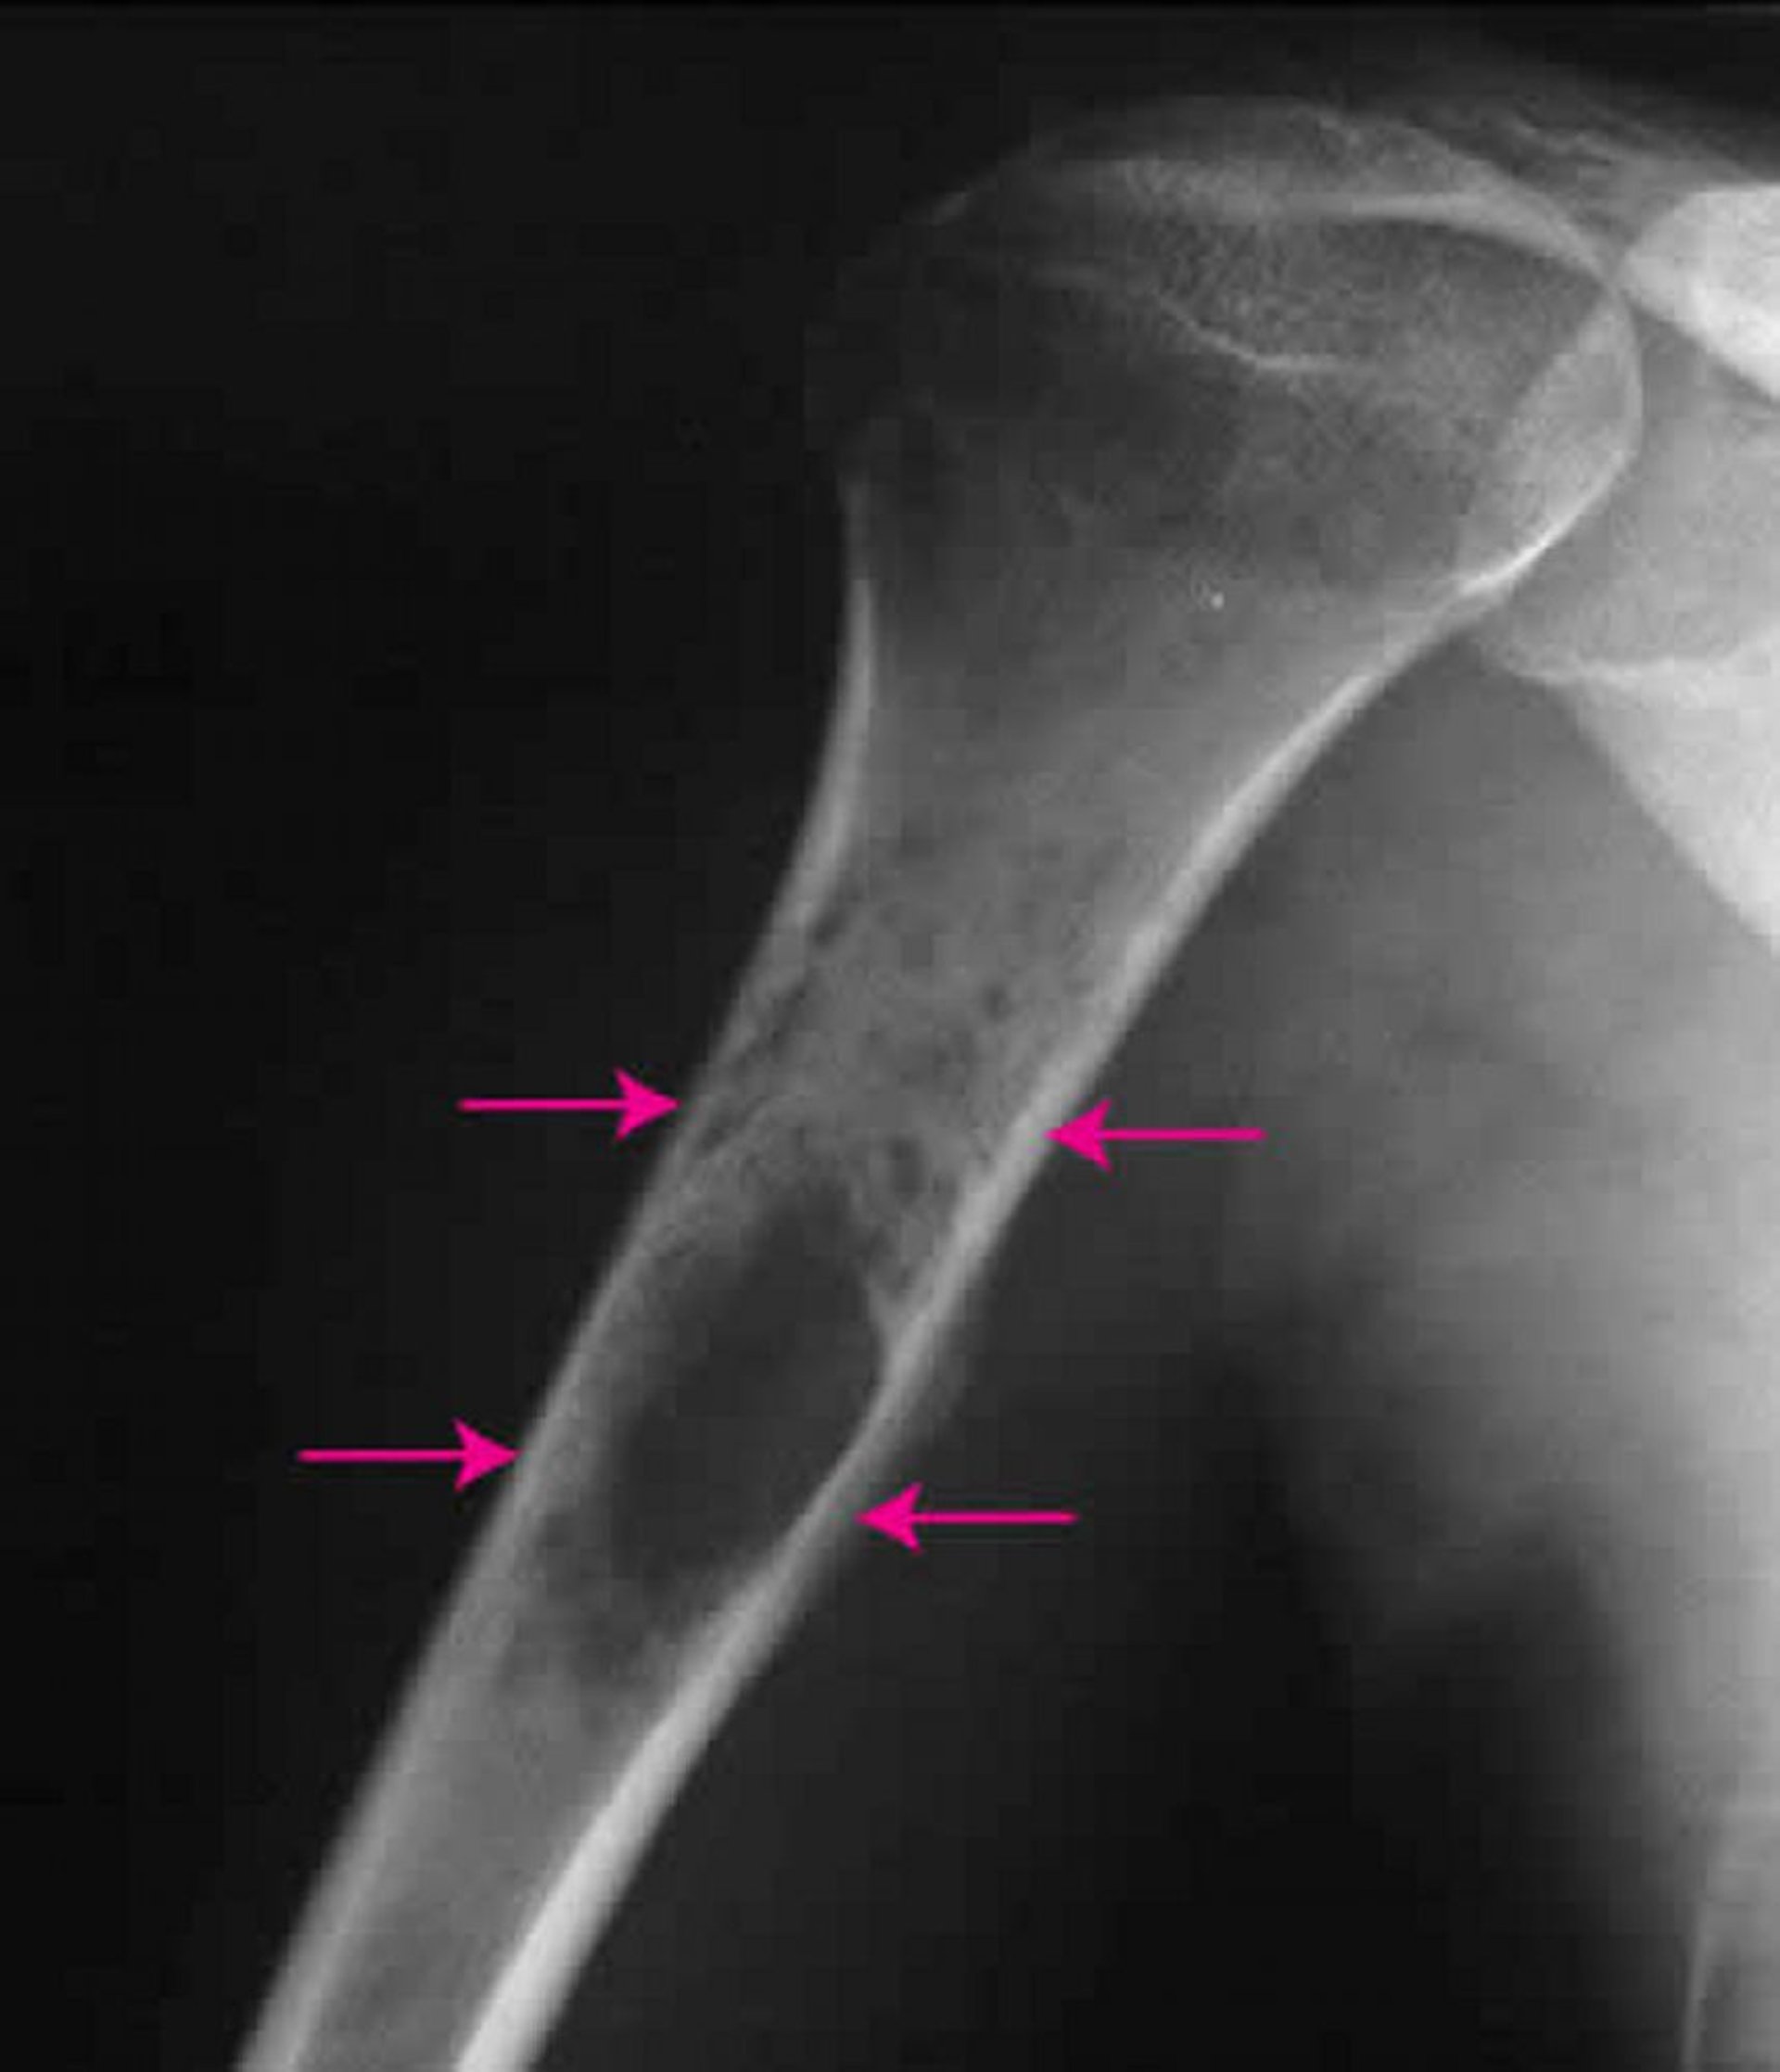

ساركومة يوينغ Ewing sarcoma of bone ورمٌ سرطانيٌّ يُصيبُ الذكورَ أكثر من الإناث غالبًا، ويبدو أكثر شُيُوعًا عند الذين تتراوح أعمارهم بين 10-20 عامًا.تحدث معظمُ هذه الأورام في الذراعين أو الساقين، ولكنَّها قد تصيب أيَّ عظم.ويُعدُّ الألم والتورُّم العَرَضين الأكثر شُيُوعًا.قد تصبح الأورام كبيرةً جدًّا، مما يؤثر في الطول الكلِّي للعظام أحيانًا.قد يتضمن الورم كتلةً كبيرةً من النسيج الرَّخو.

يُوصي الأطباءُ بإجراء صورة بالأشعَّة السِّينية لتشخيص ساركومة يوينغ.ورغم أنَّ الأشعَّة السِّينية يمكن أن تُظهِر بعض التفاصيل، إلَّا أنَّ التصوير بالرنين المغناطيسي قد يساعد على تحديد الحجم الدقيق للورم.يقوم الأطباء بأخذ خزعةًٍ لتأكيد التَّشخيص.

جرى استخدام الصورة بعد موافقة أصحابها Michael J.Joyce, MD, and Hakan Ilaslan, MD.